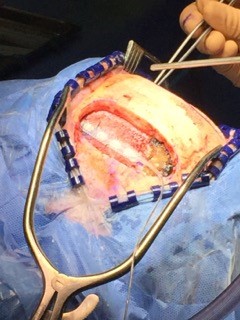

Le CHUM a été récemment le théâtre d’une première mondiale en matière de soin de la catatonie périodique avec l’implantation d’électrodes sur un patient catatonique réfractaire.

En novembre 2015, après avoir demandé l’avis d’expert et étudié la question sur le plan éthique, nous avons implanté au patient des électrodes positionnées dans l’espace épidural sur la dure-mère, la plus externe et la plus résistante des trois méninges. La stimulation bilatérale du cortex dorsolatéral préfrontal permet désormais une modulation continue et ajustable grâce à un lien avec un « pacemaker » implanté sous la clavicule du patient.

C’est la première fois que cela s’effectuait sur un sujet catatonique réfractaire. Cette importante innovation a été rendue possible grâce à l’expertise de l’équipe de neuromodulation du CHUM et de la neurochirurgienne Marie-Pierre Fournier Gosselin. L’équipe du CHUM psychiatrie-neuromodulation est composée d’infirmières et de deux psychiatres, Paul Lespérance (trouble affectif) et moi-même Emmanuel Stip (psychoses).